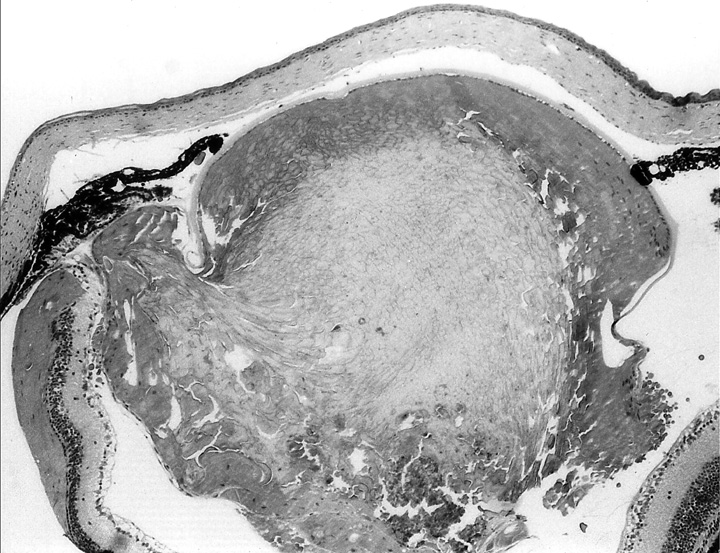

Figure 1b. Higher power view of lens in Fig. 1a.

The lens fibers are disorganized and some retain the nuclei.